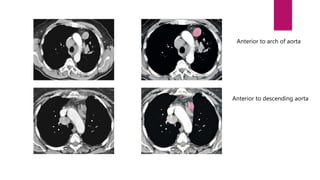

Anterior to arch of aorta

Anterior to descending aorta

Anterior to archof aorta Anterior to descending aorta

3A . Prevascular On the right:  Upper border: Apex of chest.  Lower border: Level of carina.  Anterior border: Posterior aspect of sternum.  Posterior border: Anterior border of superior vena cava.  On the left:  Upper border: Apex of chest.  Lower border: Level of carina.  Anterior border: Posterior aspect of sternum.  Posterior border: Left carotid artery